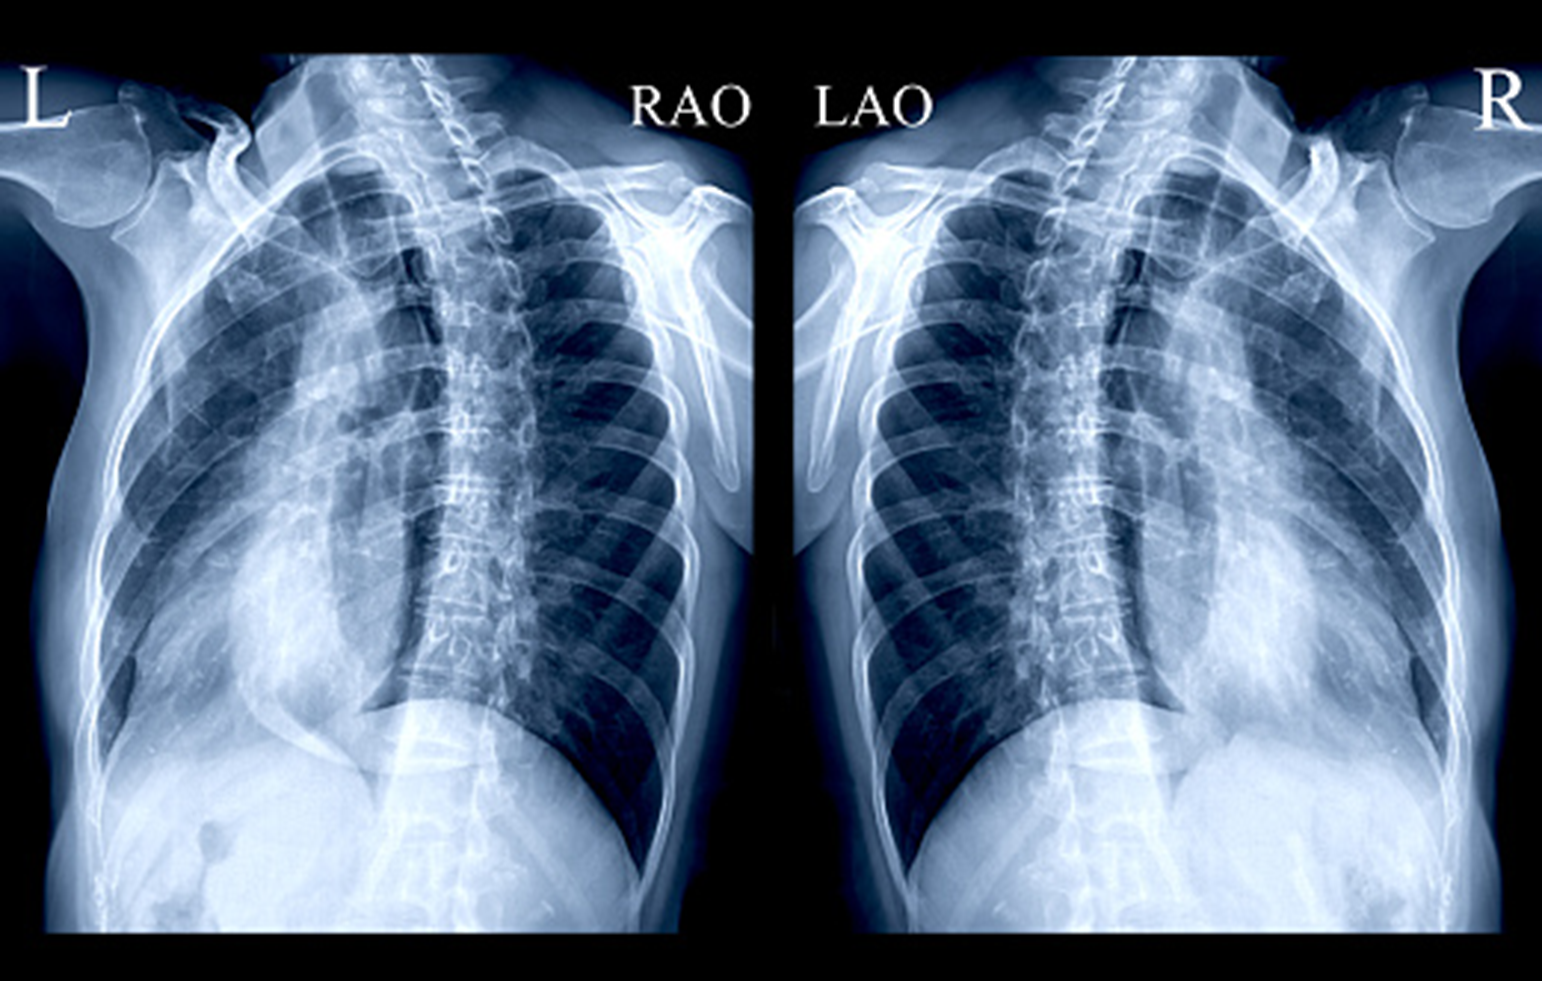

What view is this

sternal posterior oblique